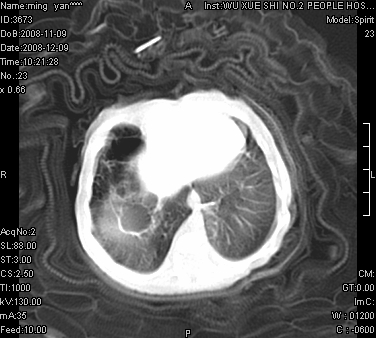

女.30天.咳嗽.喘3天.系三胞胎

考虑右肺下叶先天性肺囊肿,不除外合并右中叶肺发育不全

伴双肺感染

考虑右肺下叶先天性多发性肺囊肿可能。

考虑右肺下叶肺囊肿伴感染,右中叶节段实变或发育不全

这是一个先天性囊性腺瘤样畸形(congenital cystic adenomatid malformation,ccam),属于先天性肺发育异常,最近国外文献重新命名为先天性肺气道畸形(congenital pulmonary airway malformation,cpam),根据发生部位和畸形组织与气管、支气管的关系分成五型。本病以1岁以下婴儿多见,男性多于女性。病因为终末呼吸单元的异常增殖,形成多囊状结构。国内根据影响和病理表现分三型:ⅰ型为单个或多个大囊肿,直径大于2cm;ⅱ型为多个小囊肿,直径小于2cm;ⅲ型为大的非囊肿性病变,但显微镜下观察可见肿块由多发小囊组成(直径小于2mm)。本病可发生于肺内任何一部分,单侧肺占95%,中叶病变相对较少。

考虑右肺下叶先天性肺囊肿;右肺中叶节段性肺不张或发育不全。